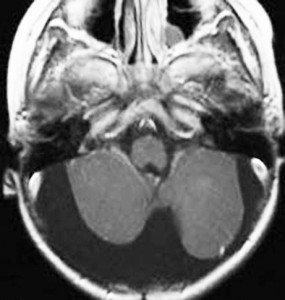

pilocerebel-2pilocerebel-1pilocerebel-3

7歳の子の小脳虫部腫瘍です。左と中央のMRIをみると一見,髄芽腫に見えます。でもこれは毛様細胞性星細胞腫で,手術で全部取れて,後遺症もなく治りました(右側)。inverted T2(左側のCISS)では黒く(低信号)に写って小脳との境界が明瞭です。

T1強調画像のガドリニウム増強(左)ではわかりませんが,右のT2強調画像で腫瘍部分がとても白く(強い高信号)に写っているのが,最大の特徴です。多くの場合,T2強調画像で毛様細胞性星細胞腫の診断がつきます。このようなT2でかなり強い高信号になるものは毛様粘液性星細胞腫の成分を含むことが多いです。